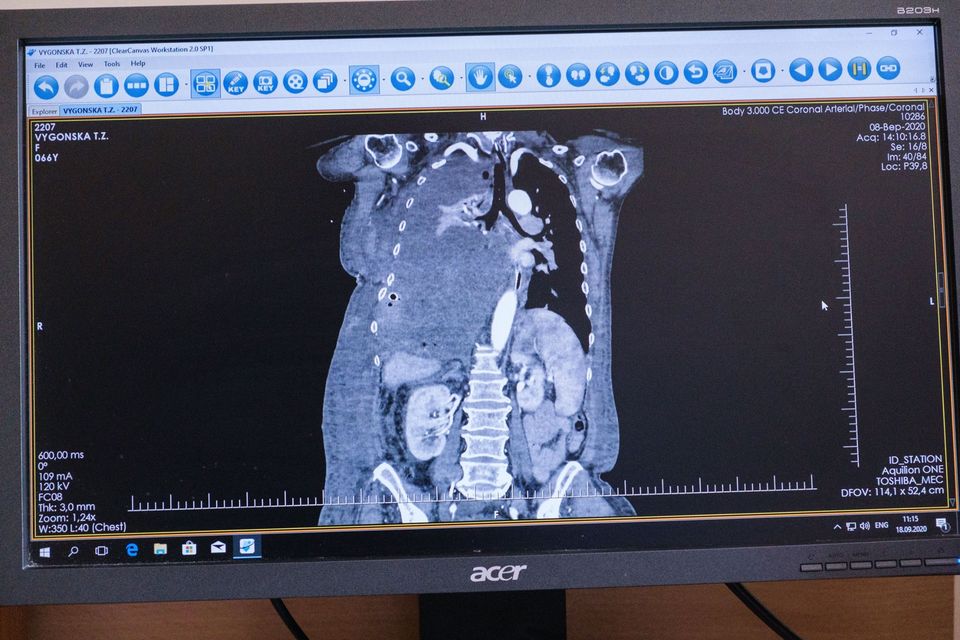

"В мае Татьяна Выгонская почувствовала сильную одышку и слабость, поэтому была вынуждена обратиться за медицинской помощью по месту жительства, а оттуда ее отправили в Хмельницкую областную клиническую больницу, где провели обследование и взяли ряд анализов. Диагноз - солитарная фиброзная опухоль правого гемиторакса. Новообразование было таким большим, что срослось, зажало правое легкое и давило на левое легкое и сердце. Из-за размера опухоли женщину отказались оперировать, а местный онколог посоветовал проконсультироваться у хирурга Виталия Соколова в Киеве", - говорится в тексте сообщения.

В "Феофании" медики провели операцию по удалению 4,5-килограмовой опухоли. Фото: facebook.com/president.gov.ua